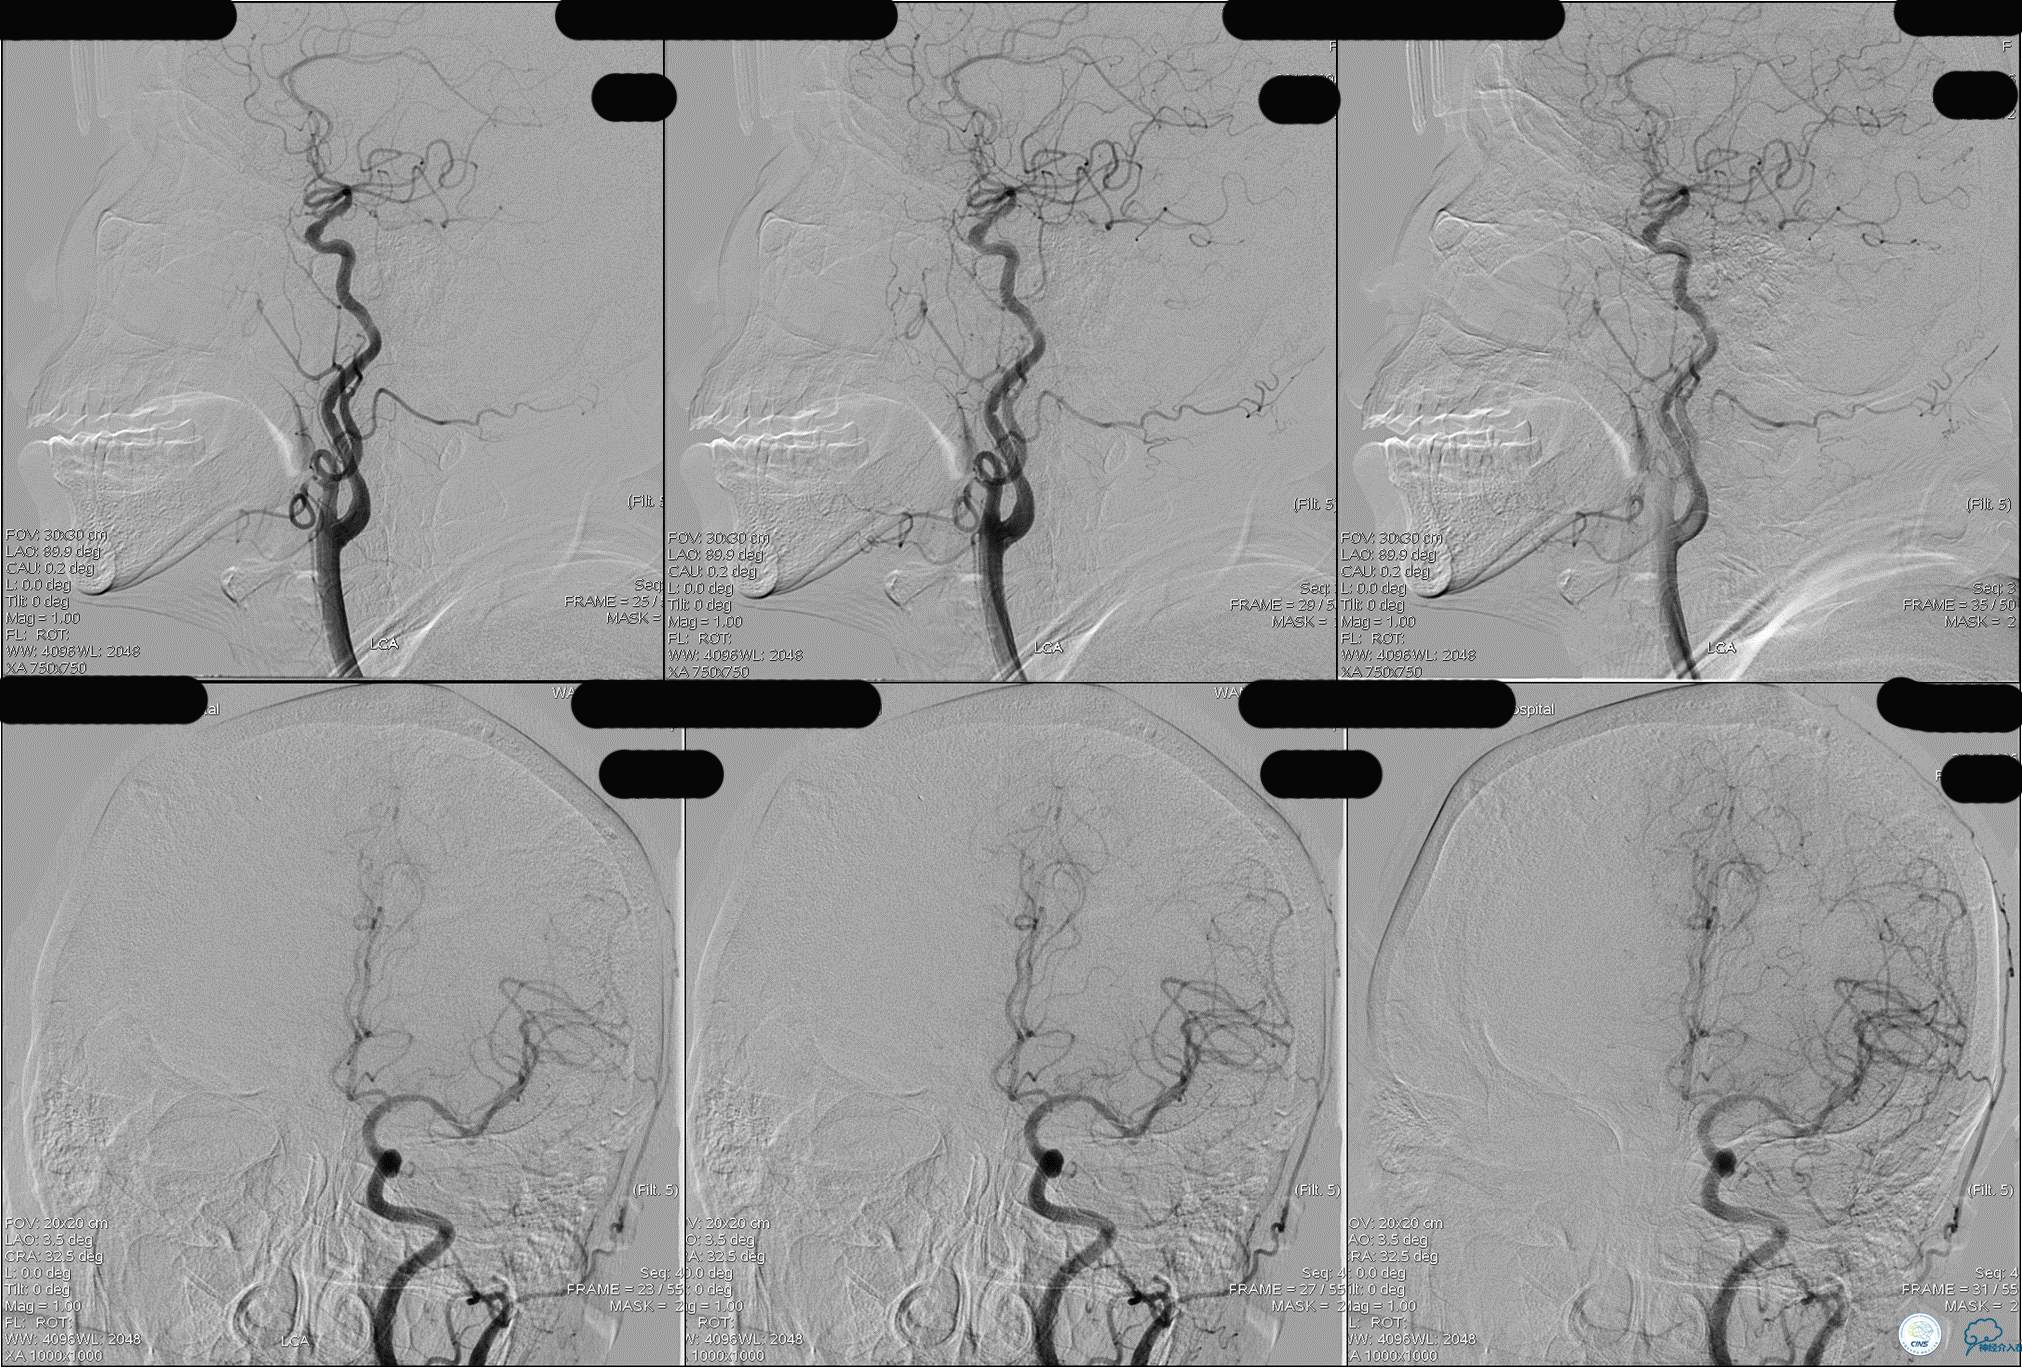

发病5.5小时给予股动脉穿刺

发现股动脉入路很差,考虑经桡穿刺。

》DSA资料(左侧颈动脉)

》DSA资料(经桡动脉,5F导引导管)

》DSA资料(前2次取栓,未取出,soli 4-20)

》DSA资料(第3次取栓)

第3次取出血栓

》DSA资料(第3次取栓后,发病10h)

》DSA资料(视察30min后,左椎造影)

★后循环取栓病人,若股动脉入路较差,可以考虑经桡动脉进行。

★基底动脉尖端的血栓偏向哪侧,应该将Solitaire支架放入同侧的大脑后动脉,这样取栓的成功率较高一些。